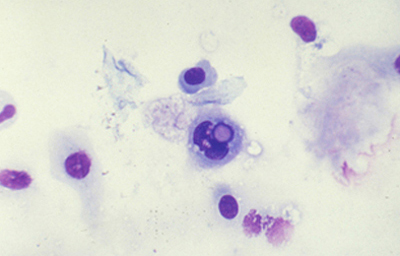

Tanto las Acanthamoebas vivas como sus productos de degradación son marcadamente antigénicos. En la respuesta celular a la infección por Acanthamoeba, los macrófagos las fagocitan (Fig 19) y los neutrófilos las destruyen vía secreción de mieloperoxidasas. (Figura 20) (Para no frenar la respuesta celular, preferimos no usar corticoides en el tratamiento de la infección activa). (El uso crónico de corticoides, en casos con superficie corneal alterada, es un factor primario en el desarrollo de una queratopatía cristalina infecciosa). La respuesta celular tiene como consecuencia, cuando la invasión por Acanthamoebas es estromal, que la abscesificación del estroma continuará aumentando a pesar del tratamiento, siendo su resolución lenta. (Figura 21, 22, 23, 24, 25, 26) (Figura, 27, 28, 29 y 30)

Fig. 19 Acanthamoeba fagocitada por macrófago. Giemsa, Original x160